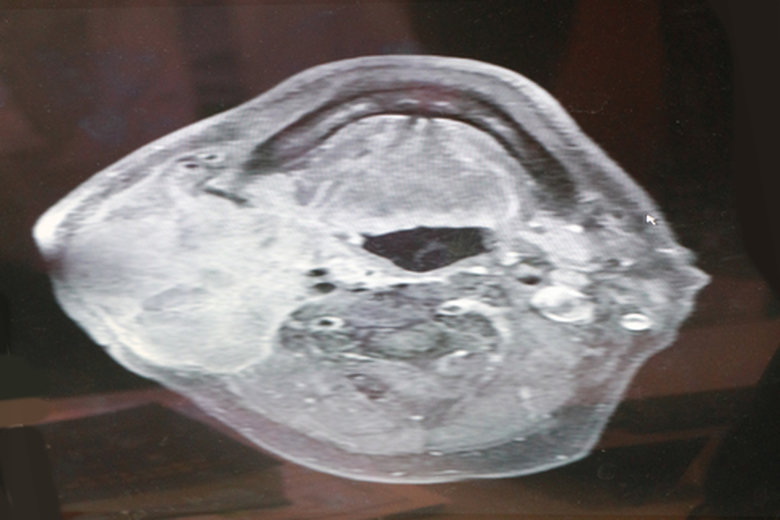

【新唐人亞太台 2017 年 01 月 06 日訊】一名60多歲男子半年多來,右側頸部腫塊持續變大,到嘉義基督教醫院耳鼻喉科就診,經切片檢查證實,罹患口咽癌合併頸部淋巴轉移第四期。

嘉義基督教醫院耳鼻喉科醫師葉峻維表示,一般民眾如果有嚼食檳榔提神暖身的習慣,再加上抽菸和喝酒,研究顯示罹患頭頸癌、尤其是口腔癌的機率是正常人的123倍。癌症初期症狀表現多元,包括喉嚨痛、吞嚥困難、聲音沙啞,口腔黏膜超過兩週未癒合的潰瘍、凸起或斑點、甚至只以耳鳴、耳部悶塞感、單側鼻塞或反覆性流鼻血來顯現。臨床上如果發現不對稱的頸部腫塊,通常是癌細胞已由原發部位轉移至頸部淋巴結。

葉峻維提醒,民眾如果有抽菸、喝酒和嚼食檳榔的習慣,除了定期接受政府提供兩年一次免費的口腔癌篩檢(針對30歲以上)外,平時如果出現任何症狀,需盡速就醫,並接受詳細檢查。早期發現,有機會在癌前病變階段介入治療,將可提高疾病的治癒成功率,千萬不要因工作忙碌和其他原因延誤就醫的黃金期。

葉峻維指出,頭頸癌的治療方針,除了手術之外,還包括化學治療及放射線治療。因此,呼籲病患和家屬,若有疑慮,應盡速尋求專業醫師協助,並與醫師詳細討論治療方針,才是最上策。